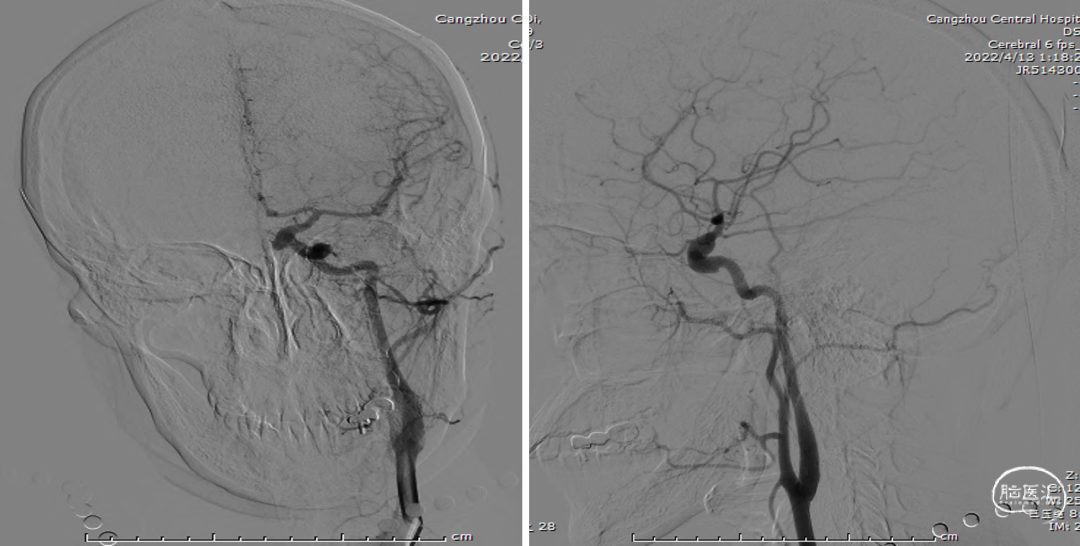

全脑血管造影(2022-04-13)

右颈内动脉3D重建(海绵窦段宽径7.2mm)

全脑血管造影

左颈内动脉3D重建图像(眼段宽径7.8mm)

左颈内动脉3D重建图像(海绵窦段宽径6.5mm)